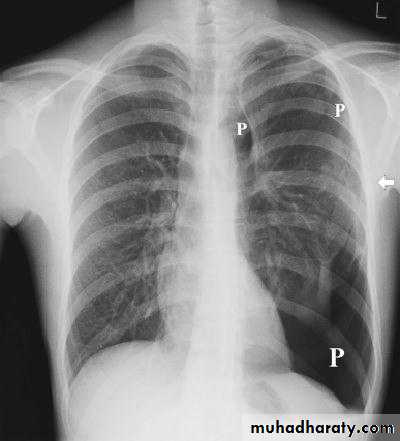

PNX inCystic lung

disease

CT adds information regarding the presence or absence of pleural fluid and underlying pulmonary disease.Diseases of the Pleura Dr.Mustafa Nema. Baghdad College of Medicine 2013

emphysematous bulla (not PNX)